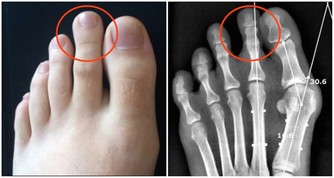

早衰,健忘失眠,食欲不振,骨骼與關節疼痛,腰膝酸軟,不耐疲勞,乏力,視力減退,聽力衰減。